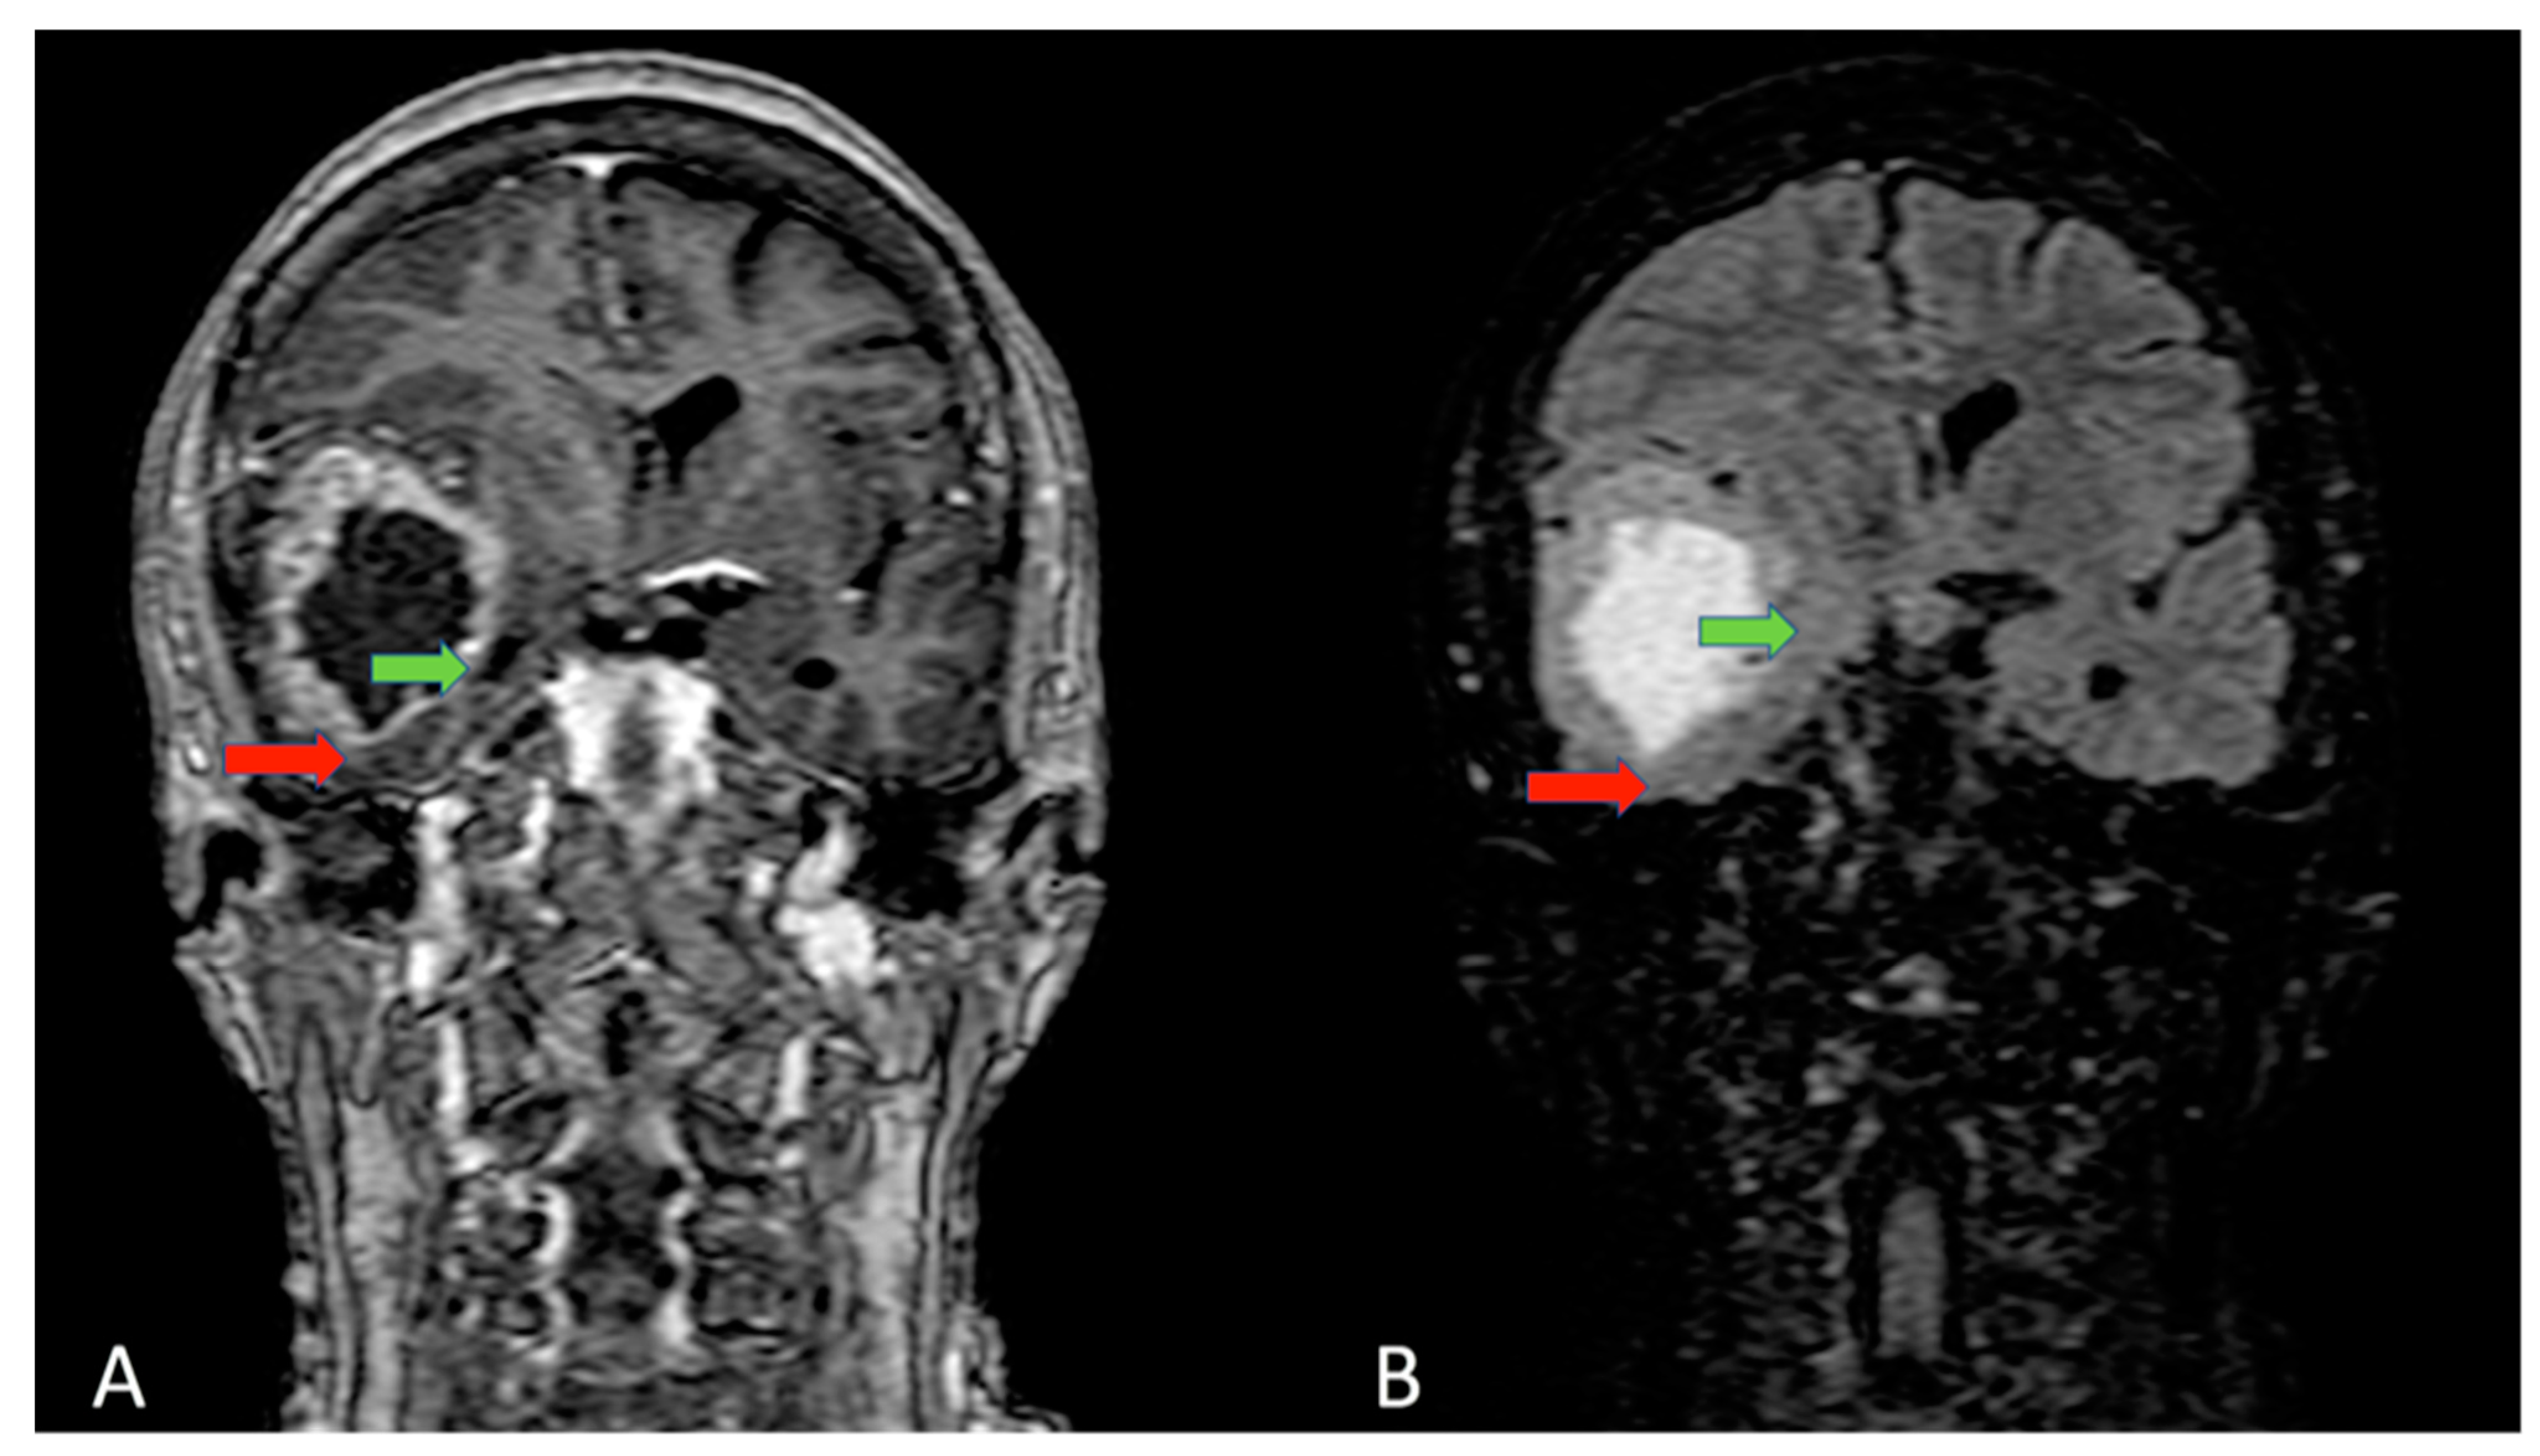

- Bohman, L.-E.; Swanson, K.R.; Moore, J.L.; Rockne, R.; Mandigo, C.; Hankinson, T.; Assanah, M.; Canoll, P.; Bruce, J.N. Magnetic resonance imaging characteristics of glioblastoma multiforme: Implications for understanding glioma ontogeny. Neurosurgery 2010, 67, 1319–1327. [Google Scholar] [CrossRef] [PubMed]